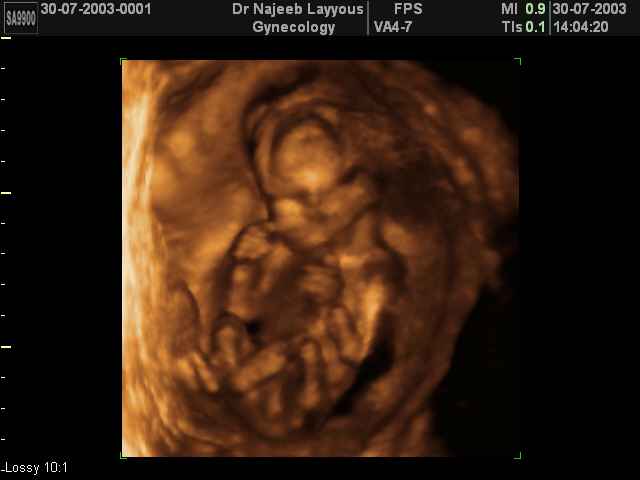

- Fetal Behavior Ultrasound Photos

Ultrasound Photos in 3D showing Fetal Behavior Inside the uterus | Dr N Layyous